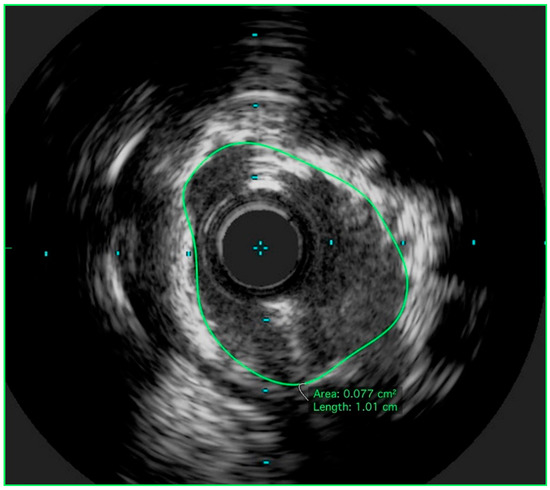

3. Technical Considerations: The Role of Intravascular Ultrasound in UPLM PCI

4. Achieving Adequate Left Main Minimal Luminal Area